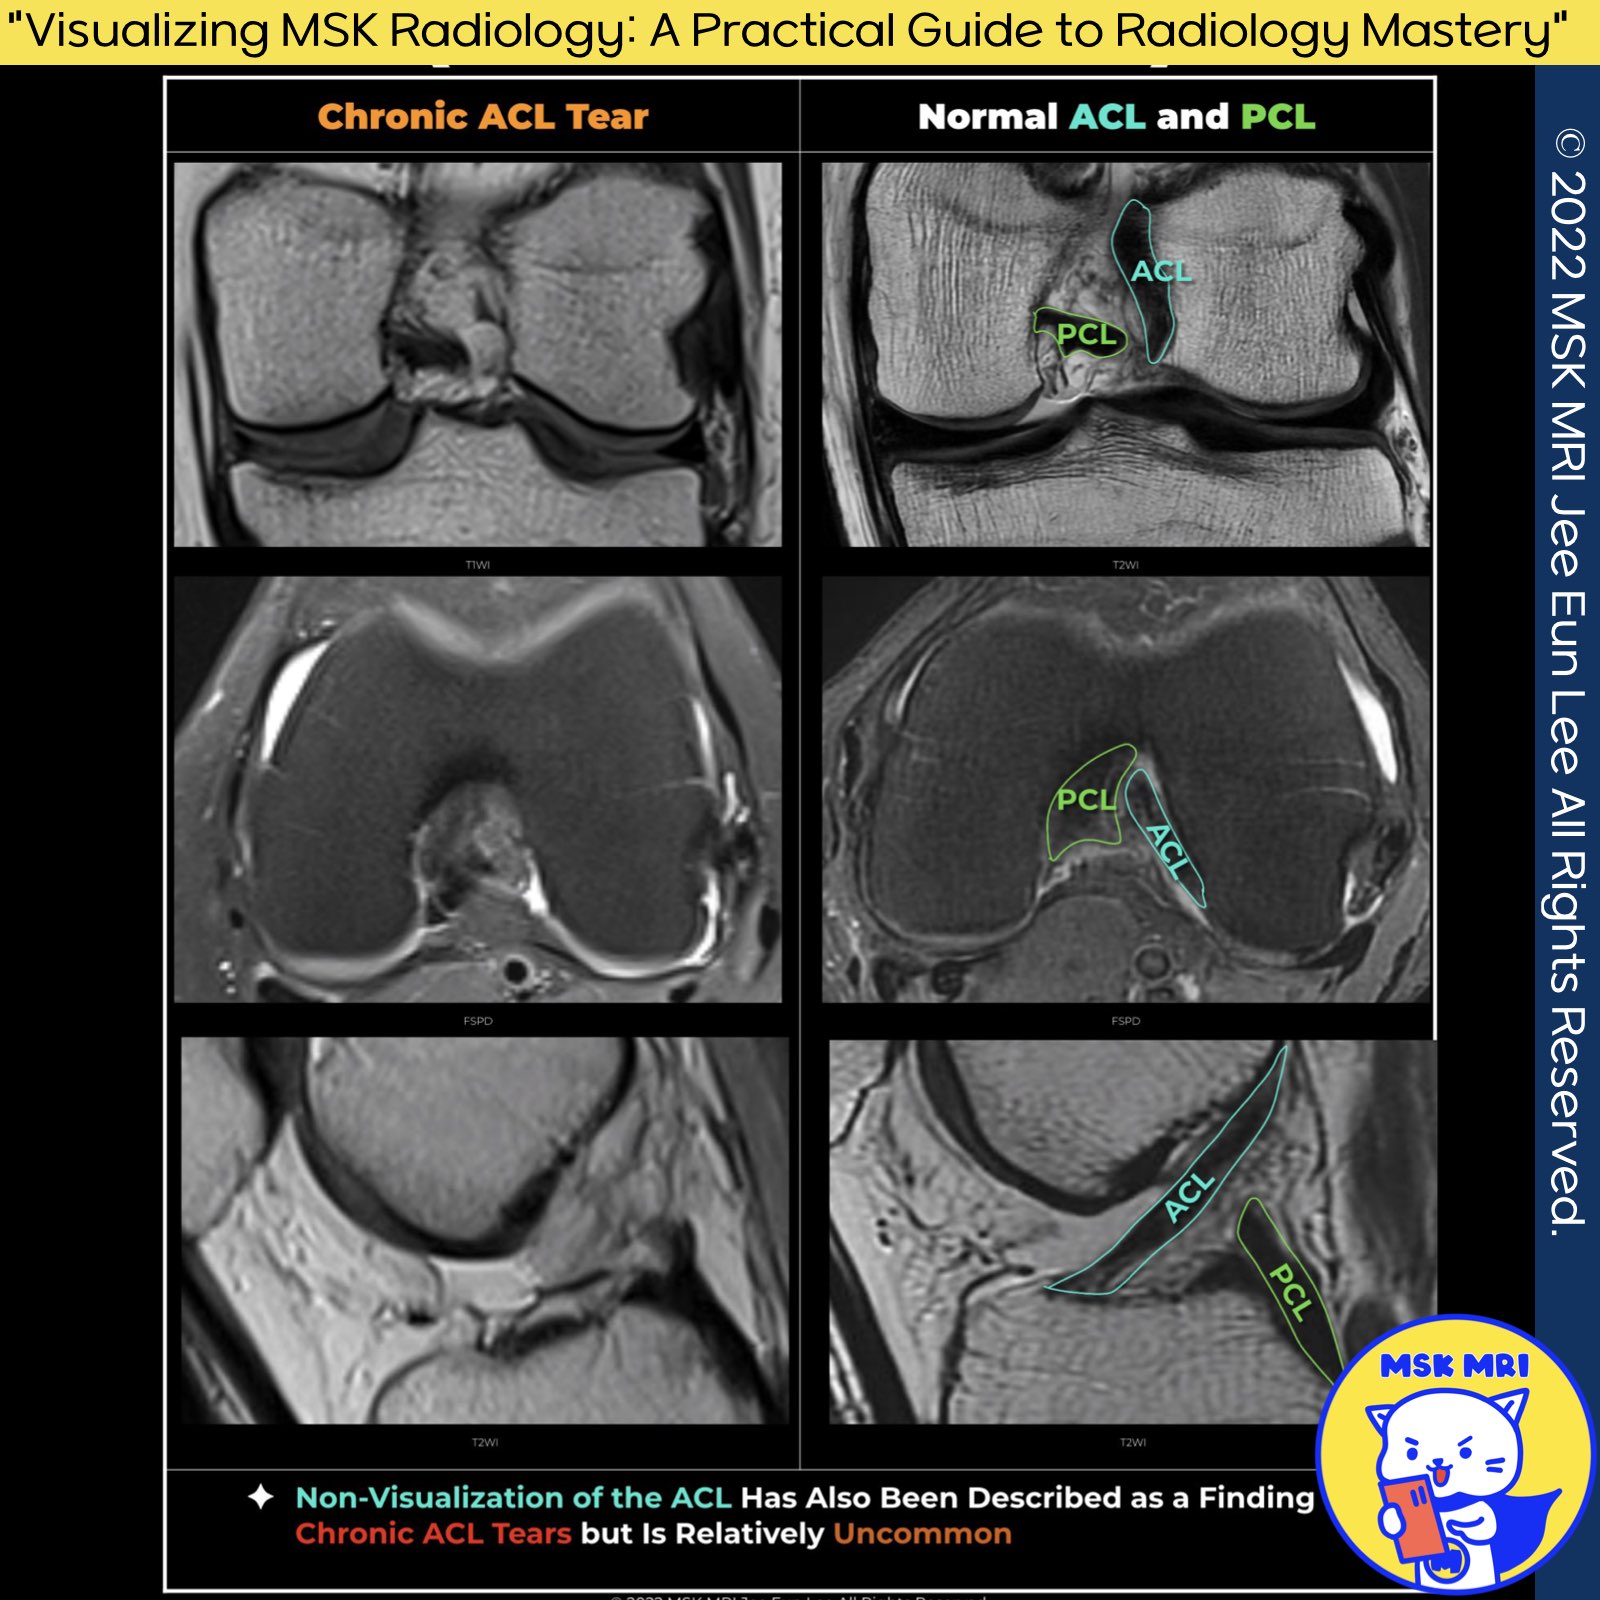

★ Chronic ACL tears

- Laxity and abnormal horizontal orientation of fibers are the most useful features for detecting ACL disruption in the chronic setting as opposed to fiber discontinuity and bone contusions, which are the most useful features in the acute setting.

- Nonvisualization of the ACL has also been described as a finding of chronic ACL tears but is relatively uncommon.

- Absence of ACL tissue in the lateral intercondylar notch, indicating empty notch sian on coronal MR images (empty lateral wall)